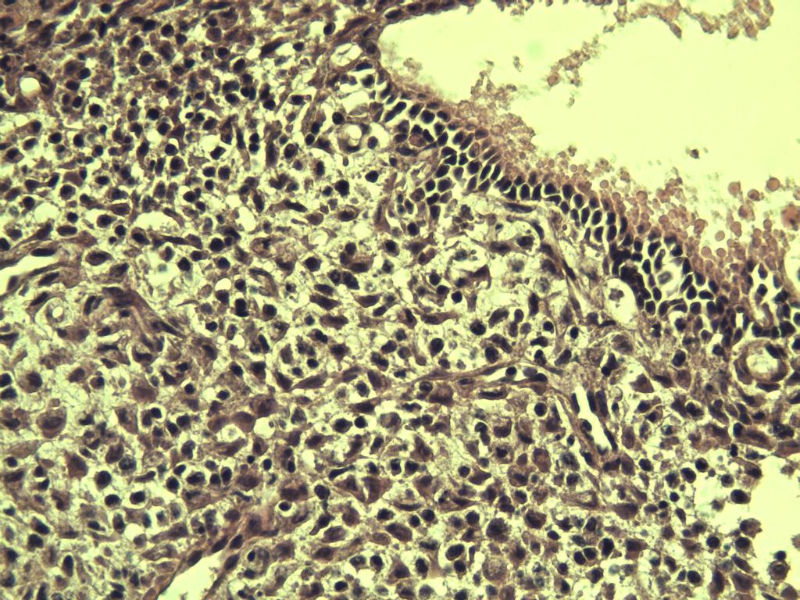

这是另外一个 40岁 经期延长 流血量增多 半年 这是蜕膜样变吧 有什么意义吗? 要报告不?